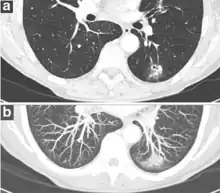

Thin slice and maximal intensity projection of a lung nodule, the latter better visualizing vascular convergence.[9]

• Vascular convergence is where vessels converge to a nodule without adjoining or contacting the edge of the nodule, and is mainly seen in peripheral subsolid lung cancers.[9] It reflects angiogenesis.[9]